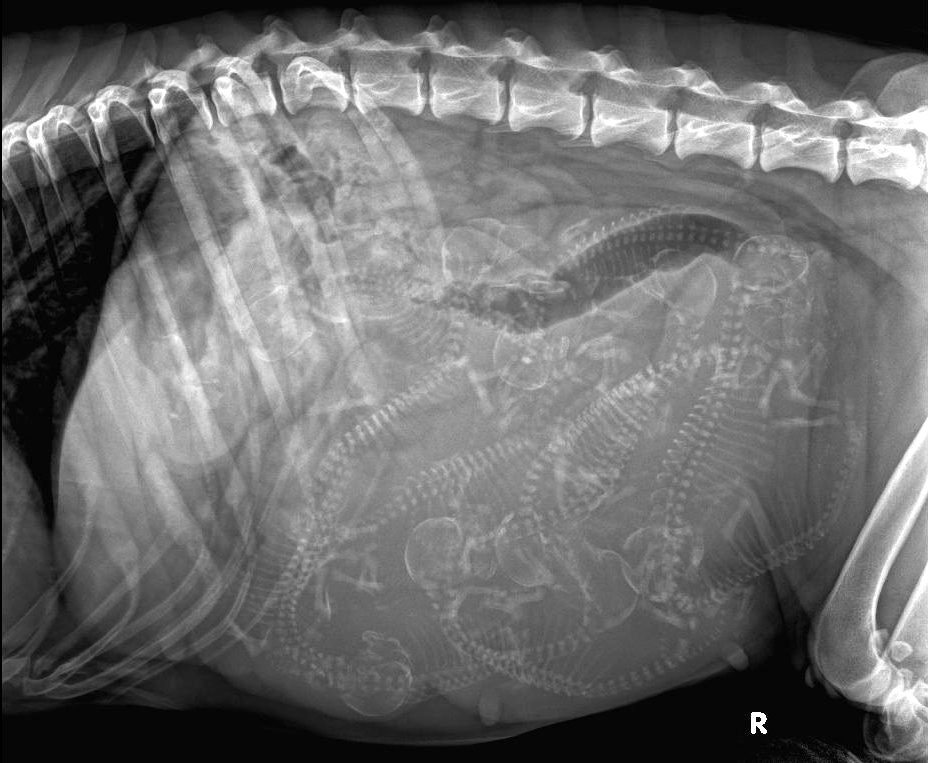

RTG snímek 54. den – bříško plné štěňátek 🙂